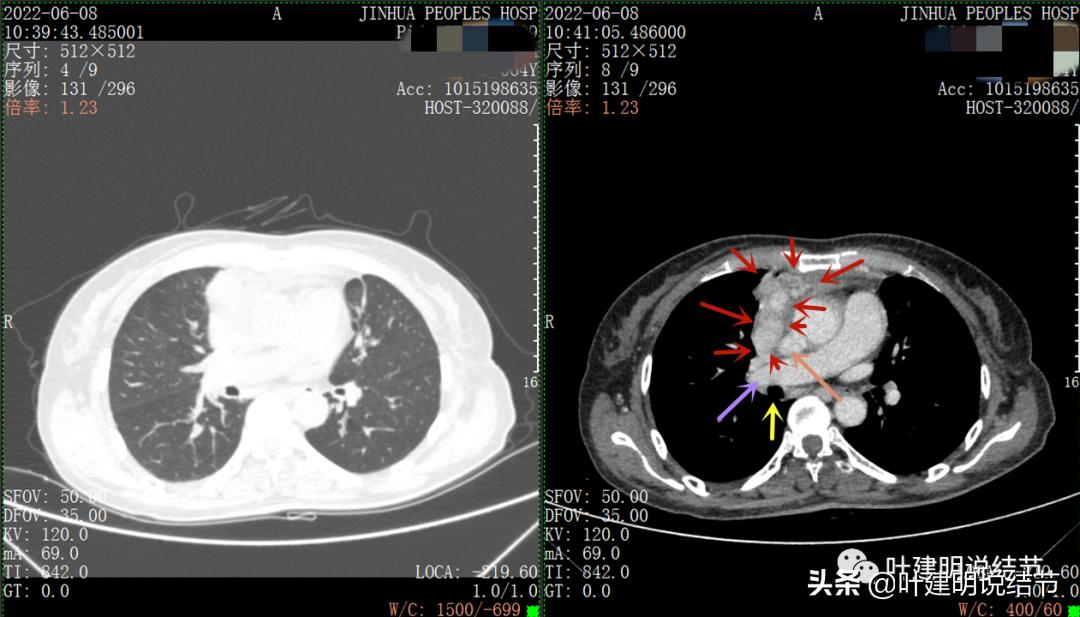

再来看看她的CT增强图像:

以下图片左侧是肺窗,右侧是纵隔窗。红色箭头示病灶,桔色箭头示无名静脉,黄色箭头示支气管,砖色箭头示上腔静脉,蓝色箭头示主动脉,紫色箭头示肺动脉。

绿色箭头示近膈面处,心脏边病灶

此灶与主病灶不是完全相连的

病灶占据前纵隔从上到下全程,多中心,密度不均,对心脏与大血管有压迫,没有明显侵犯

病灶表面不平,中间有坏死